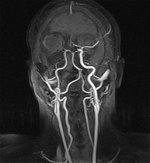

MR-Angiographie (MRA) meiner Halsgefäße |

Zwei Arterienpaare übernehmen die Blutzufuhr zum Gehirn (Arteria

carotis interna) und (Arteria vertebralis).

Beide vereinigen sich in der Hirnbasis zu einem

ringförmigen Arterienkreis, dem Circulus Willisii. Vom

Willisi-Kreis gehen paarweise die drei großen Hirnarterien ab,

die vordere, mittlere und hintere Hirnarterie. |

MR-Angiographie (MRA) meiner

Hirnbasisarterien

(Circulus Willisi) |

gut sichtbar distale Stenose Arteria

carotis rechts |

MR-Angiographie (MRA) meiner Halsgefäße Stand: 03.03.2006 |